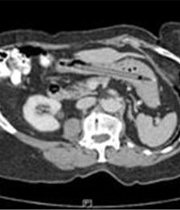

ImagenLa mujer, de 76 años y cuya identidad no fue revelada, vio hace un cuarto de siglo cómo el bolígrafo que estaba utilizando ante un espejo para observar unos puntos blancos en sus amígdalas se deslizaba accidentalmente a través su garganta.

El examen con rayos X que los médicos le realizaron entonces no mostraba el bolígrafo, por lo que nadie creyó la historia que relataba la mujer, señala el artículo del BMJ, y el utensilio permaneció alojado en su estómago hasta ahora.

Este año, una nueva revisión sí detectó el bolígrafo, que fue extraído por medio de un procedimiento endoscópico que requirió anestesia total.